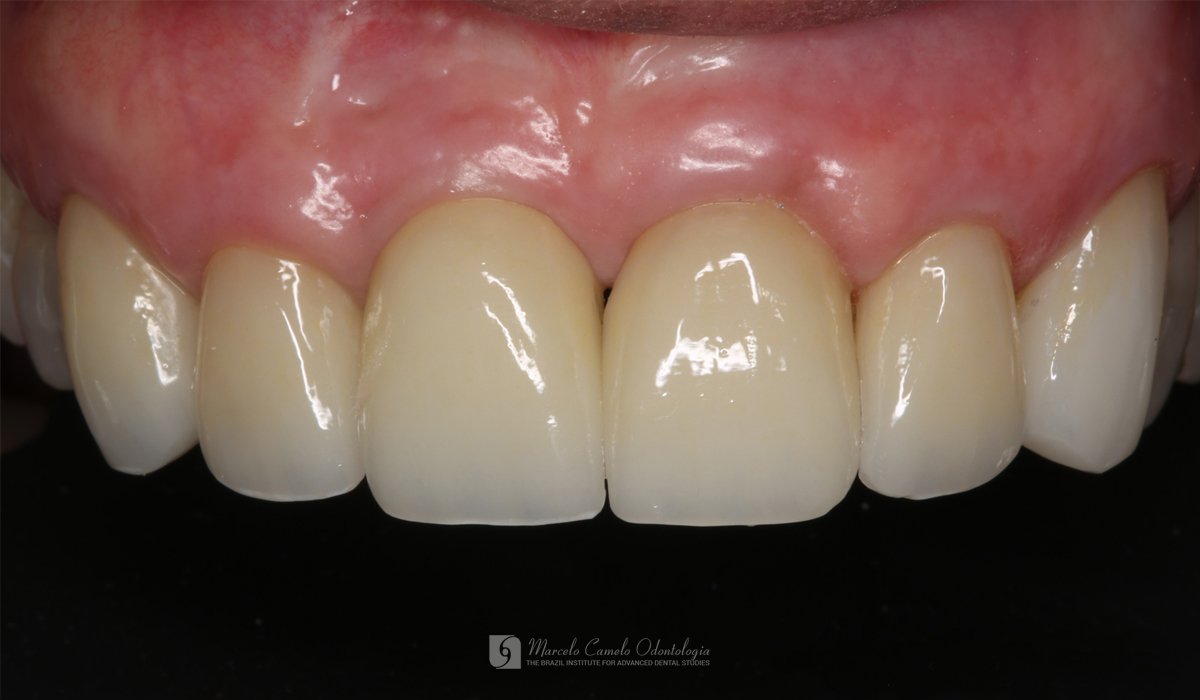

RESTAURAÇÃO SIMULTÂNEA: Óssea, gengival, após fratura da raiz dentária Última modificação do post:22 de outubro de 2025 Tempo de leitura:1 minuto de leitura Comentários do post:0 comentário * Clique nas imagens para ampliar Finalização com coroas de cerâmica.Acompanhamento de um ano. Tags: #implantes, #marcelocameloodontologia, #oralhealth, #periodontia, #periodontite, #periodontitis, #procedimentosodotonologicos, #restauraçãosimultânea, #tratamentosdentarios Leia mais artigos Post anteriorA REVOLUÇÃO EM TRATAMENTOS DE PERIODONTITE E PERIOIMPLANTES Próximo postFINALMENTE, PODEMOS SABER O QUE CAUSA A DOENÇA DE ALZHEIMER E COMO PARÁ-LA Você também pode gostar PROSPECTIVE 1-Year Study of Immediately Loaded Implants: 8-Patient Case Series Report 22 de setembro de 2025 Regeneração de Papilas-I 15 de outubro de 2025 CONTATO ENTRE OS DENTES DAS ARCADAS SUPERIOR E INFERIOR 22 de setembro de 2025 Deixe um comentário Cancelar respostaComentárioDigite seu nome ou nome de usuário para comentar Digite seu endereço de e-mail para comentar Digite o URL do seu site (opcional) Salvar meus dados neste navegador para a próxima vez que eu comentar.